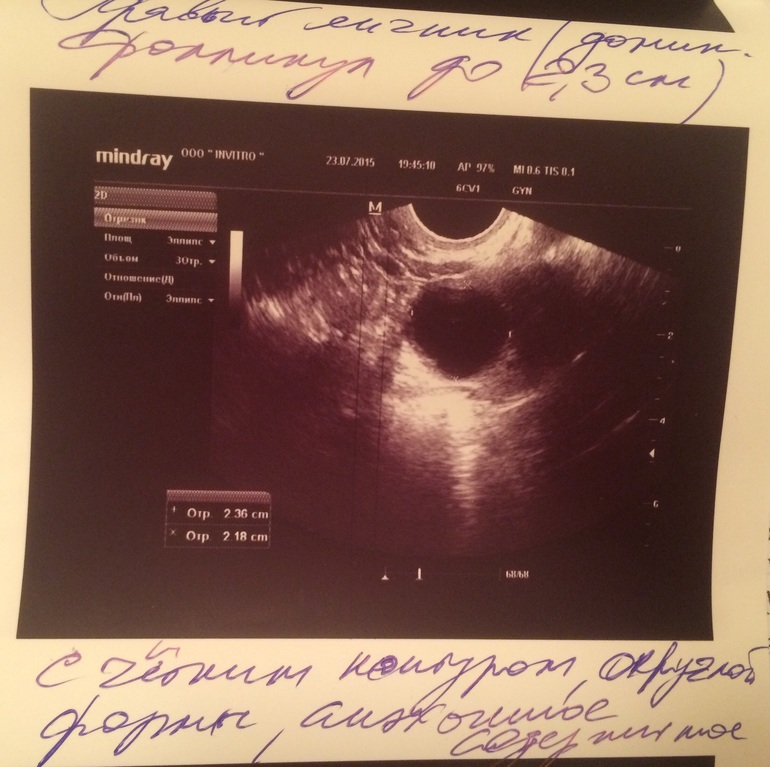

Шол 11 дц.... Неделю назад была на узи (4 дц) сказали эндик 3 мм-мало, ДФ слева 10 мм..... Я как то растроилась и пошла домой думать как же нарости ть его.... На 8 дц побежал ЯБ в огромных количествах.... Стала делать тесты

ДФ 23 мм справа, А мой самый любимый и красивый вырос

Мась это было с лева..... теперь там нет никаких 10 мм, сейчас ДФ справа 23 мм

Ммм, девочка моя! Трехслойный! 23 мм на 11 ДЦ! Шикаарно! У меня так же было в беременный цикл (если помнишь))) Тестик прям поярчал. Жди дня через 2 О. С Богом!!!! Апчхи на тебя! Заразным беременным!!!! Апчхи! У нас первые толчки как раз))) Апчхи!!!!